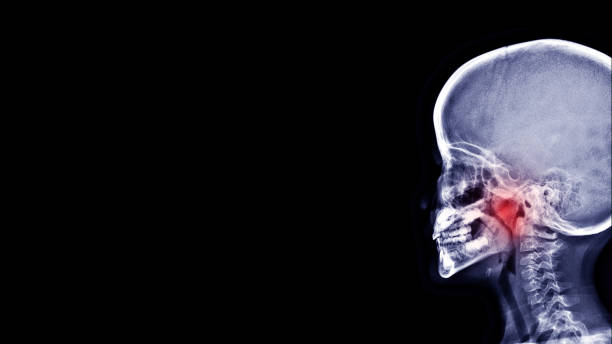

This surgery is performed through the mouth using special instruments. It does not require an incision, as the adenoids are removed through the mouth, which is kept open using a retractor. The doctor may use different methods to remove the adenoids, either through curettage to scrape off the tissue or radiofrequency heat to destroy it.